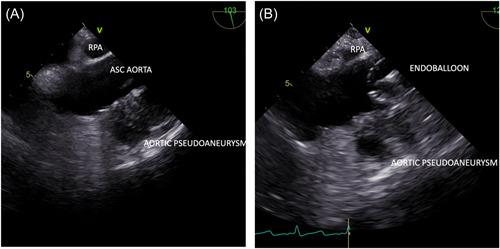

Redo cardiac surgery can present a unique set of challenges even to the experienced surgeon. Although outcomes have steadily improved in the modern era; if an intraoperative adverse event occurs, there is a 5% incidence of mortality and 19% incidence of myocardial infarction, stroke or death. Overall, the modern incidence of mortality at reoperation varies but be segregated into low and higher risk cohorts depending on the planning computed tomography imaging and risk to substernal structures on re-entry. Patients with ascending aortic or root pseudoaneurysms represent a particularly difficult subset of high-risk patients requiring reoperative cardiac surgery due to the danger of exsanguination and air embolization. The gold standard for management of such cases remains the use of deep hypothermic circulatory arrest (DHCA) to achieve safe re-entry in such cases however this can result in unpredictable DHCA duration depending on the degree of pericardial adhesions. We report a case of aortic pseudoaneurysm in a patient with patent coronary grafts managed using an endoballoon precisely positioned relative to the proximal anastomoses resulting in a safe surgical re-entry and shorter DHCA time.

再次心脏手术即使对于经验丰富的外科医生来说也可能带来一系列独特的挑战。尽管在现代时代,手术结果已经稳步改善;如果术中发生不良事件,死亡率为 5%,心肌梗死、中风或死亡的发生率为 19%。总体而言,再次手术的现代死亡率有所不同,但根据规划的计算机断层扫描成像以及重新进入时对胸骨后结构的风险,可以将其分为低风险和高风险队列。升主动脉或根部假性动脉瘤的患者由于出血和空气栓塞的危险,代表了需要再次心脏手术的高风险患者中特别困难的亚组。此类病例的黄金标准仍然是使用深低温循环停止(DHCA)来实现此类情况下的安全重新进入,但这可能导致 DHCA 持续时间不可预测,具体取决于心包粘连的程度。我们报告了一例冠状动脉移植血管通畅的患者发生主动脉假性动脉瘤的病例,使用相对于近端吻合口精确定位的内球囊进行处理,从而实现了安全的手术再次进入和更短的 DHCA 时间。